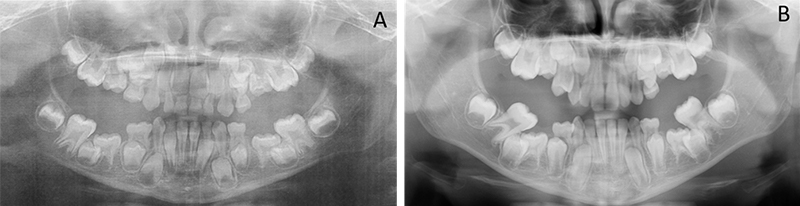

Les ankyloses des molaires temporaires sont fréquentes et doivent faire l’objet d’un suivi rigoureux afin de s’assurer de leur caractère isolé(5,6). En effet, l’ankylose des molaires temporaires peut faire partie d’un tableau clinique de DPE et constituer un des premiers signes d’appel des DPE. Le praticien doit alors être attentif et suivre l’évolution des dents permanentes au risque que la situation se dégrade (Fig. 01).

Fig. 01 : radiographies panoramiques chez un enfant présentant un défaut primaire d’éruption à 7 ans (A) et 9 ans (B).